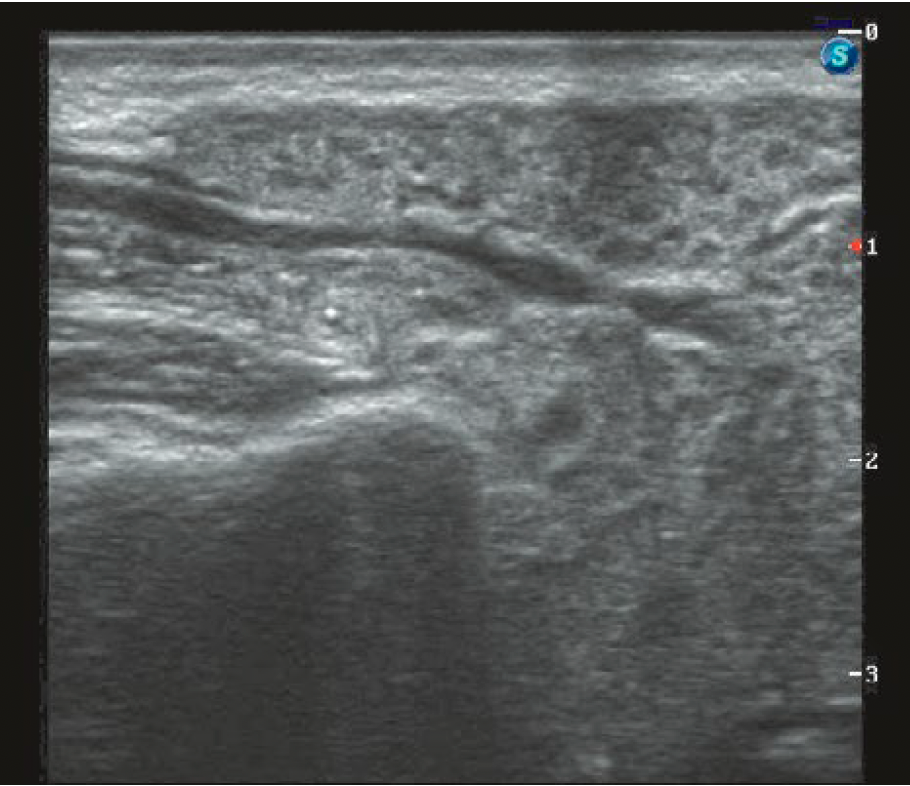

Расширение протока слюнной железы

У пациентов с поражением ОСЖ справа проявилось в 7,5% случаев, слева — у 6,7% пациентов, медиана расширения протока составила 2 мм [1,8—2,2 мм] при максимальном расширении до 3 мм (рис. 1).

Поэтому клинически мы наблюдаем сухость в полости рта, вызванную уменьшением количества слюны и застоем ее изза образования стенозов и стриктур в протоковой системе, которые уже компенсаторно способствуют образованию расширений протоков, визуализируемых с помощью УЗ-диагностики.

Таким образом, снижение эхогенности, появление неоднородности структуры, особенно ОСЖ, и расширение протоковой системы >0,8 мм являются значимыми УЗ-паттернами развития сиаладенита после РЙТ.